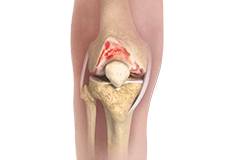

Knee Arthritis

The joint surface is covered by a smooth articular surface that allows pain-free movement in the joint. Arthritis is a general term covering numerous conditions where the joint surface or cartilage wears out. This surface can wear out for several reasons; often the definite cause is not known.